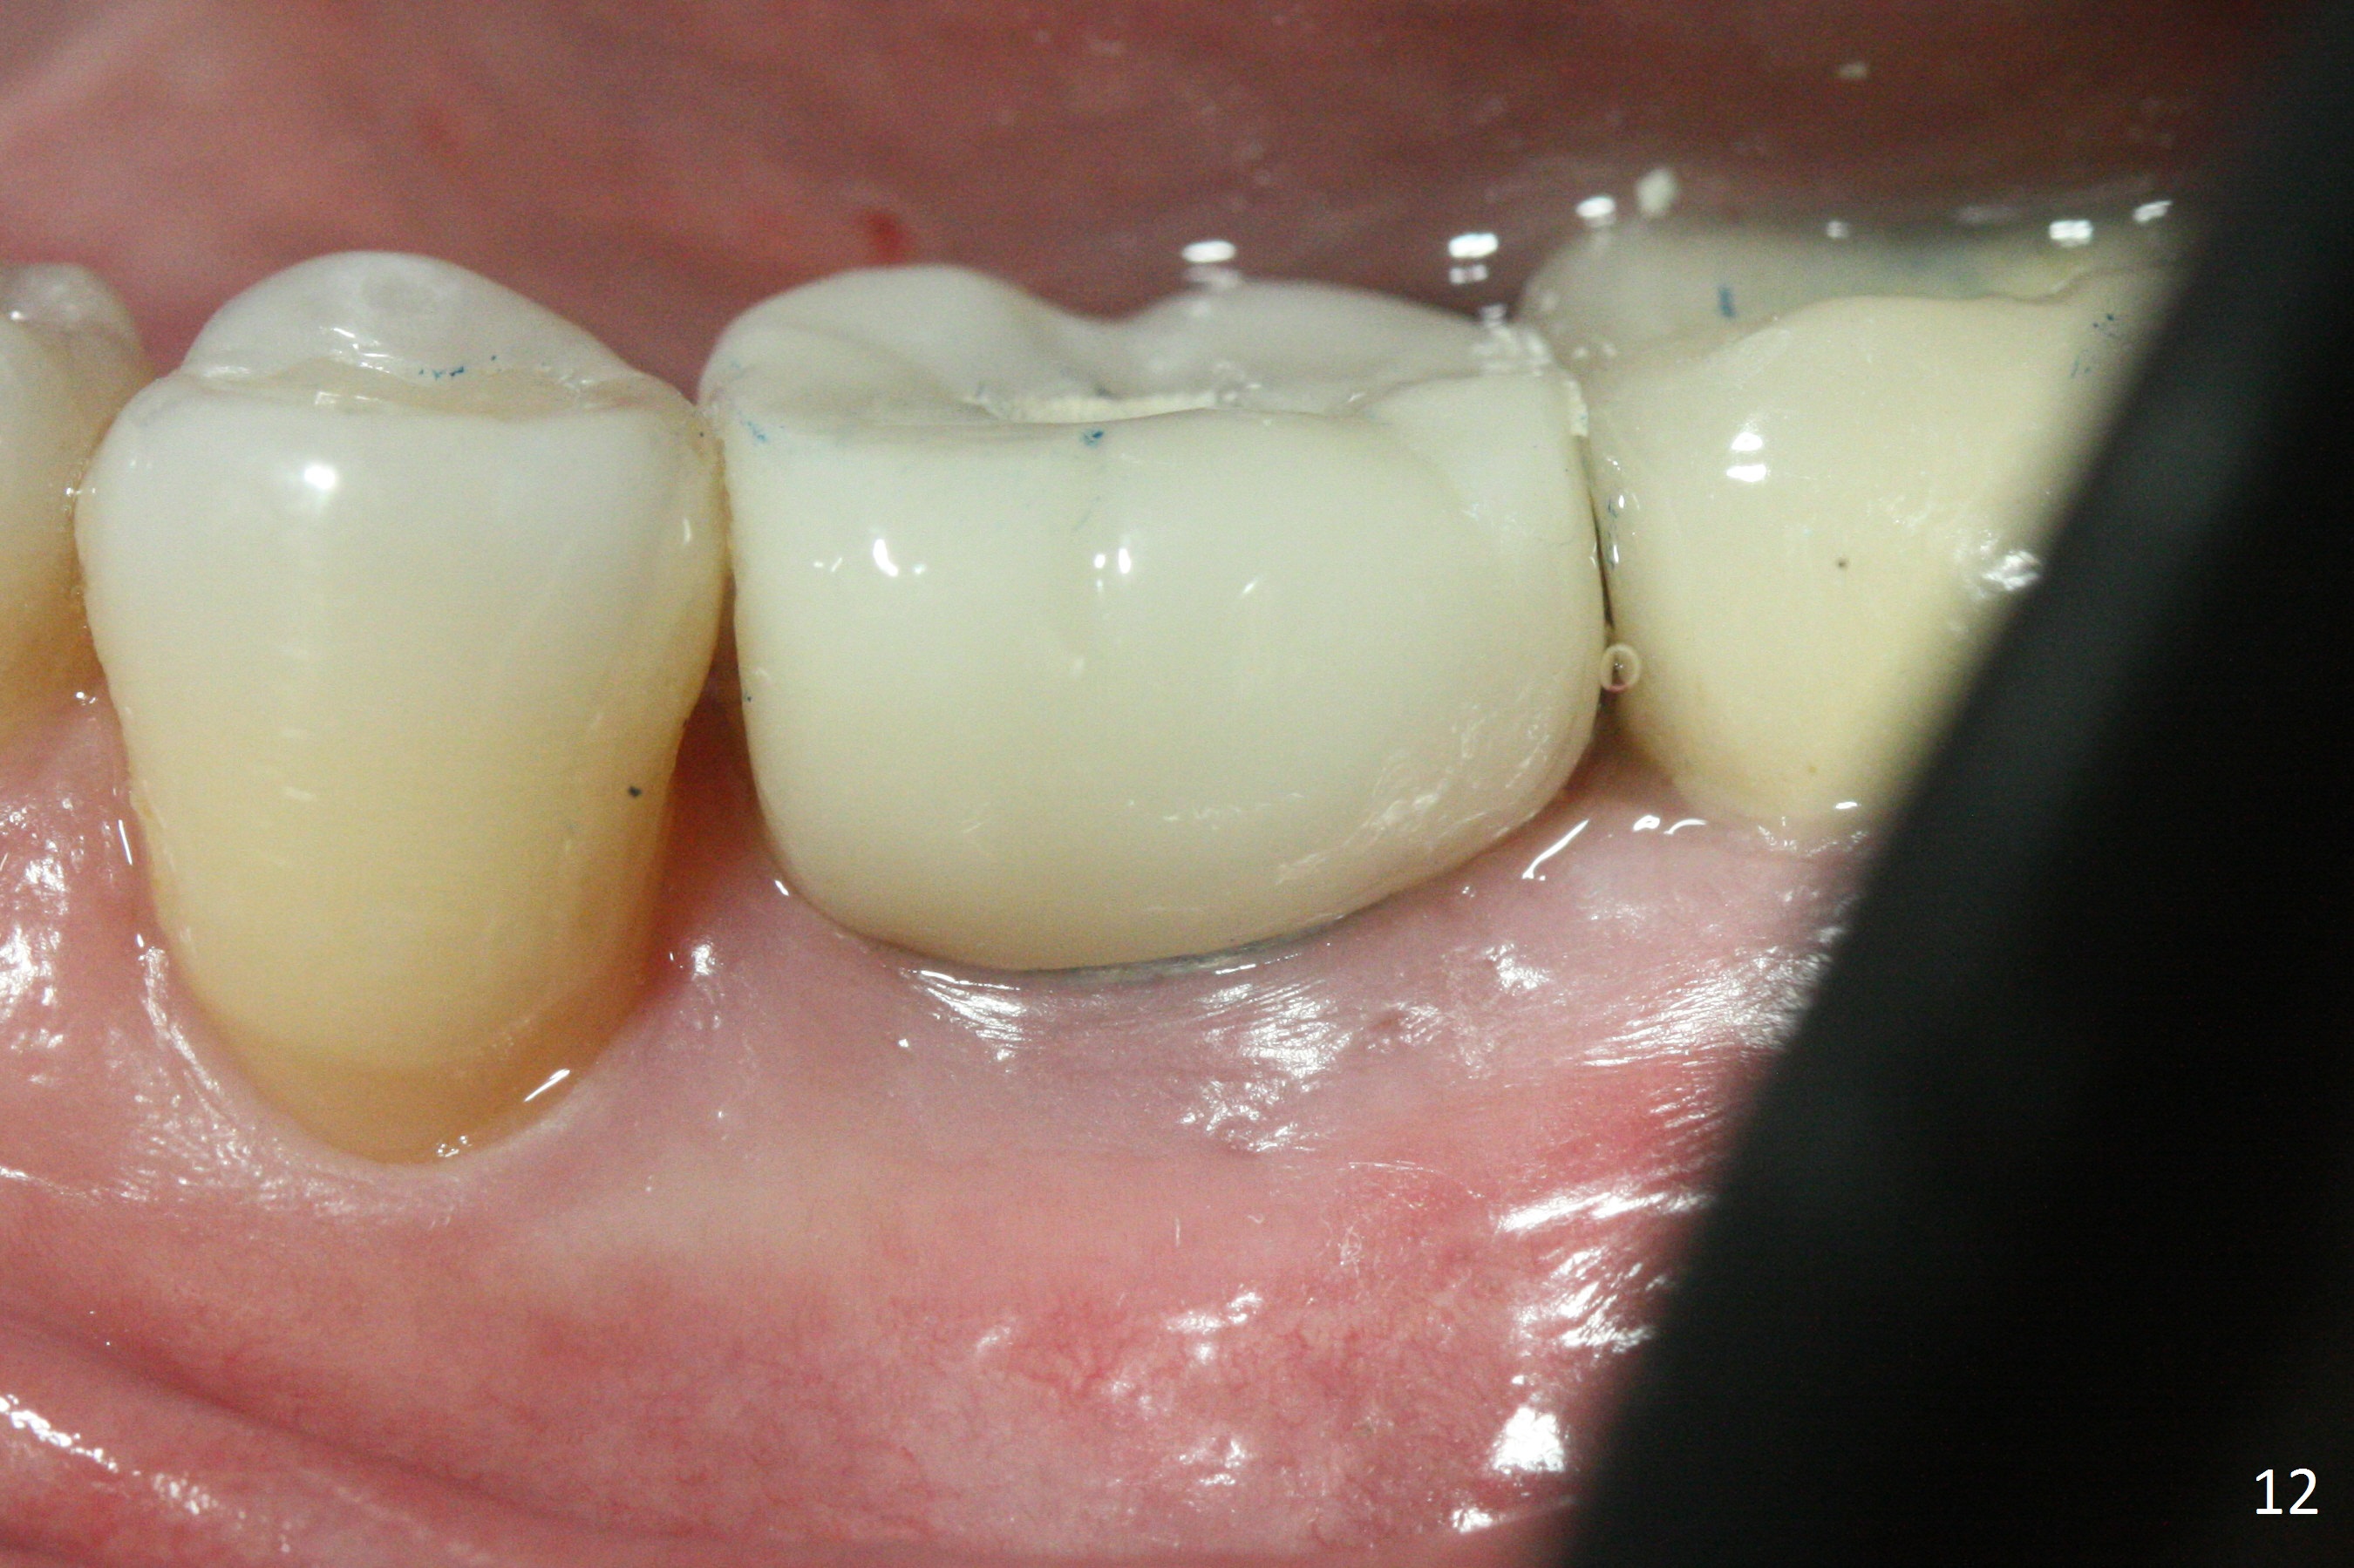

The gingiva looks healthy 8 months postop (3 months post cementation (after abutment screw retightening and addition of porcelain to proximal surfaces, Fig.12). New bone has apparently covered the implant plateau (Fig.13 arrows). Bone density between threads increases 9 months post cementation (Fig.14). There is 2 mm bone superior to the implant plateau mesial and distal 1 year 9 months post cementation (Fig.15,16). The crown/abutment is loose 3 times (3 months (Fig.14), 11 months (between Fig.14 and 15) and 2 years 3 months post cementation). In spite of being stable 3 years 10 months post cementation, a smaller abutment is placed (Fig.17 (PA), 18 (BW)) with impression for a new crown. After intraoral cementation, the new crown/abutment is removed for residual cement removal. When the complex is reseated, it is not smooth, probably due to proximal undercut. Fortunately the abutment appears to be completely seated, followed by 20 Ncm torque (Fig.19).